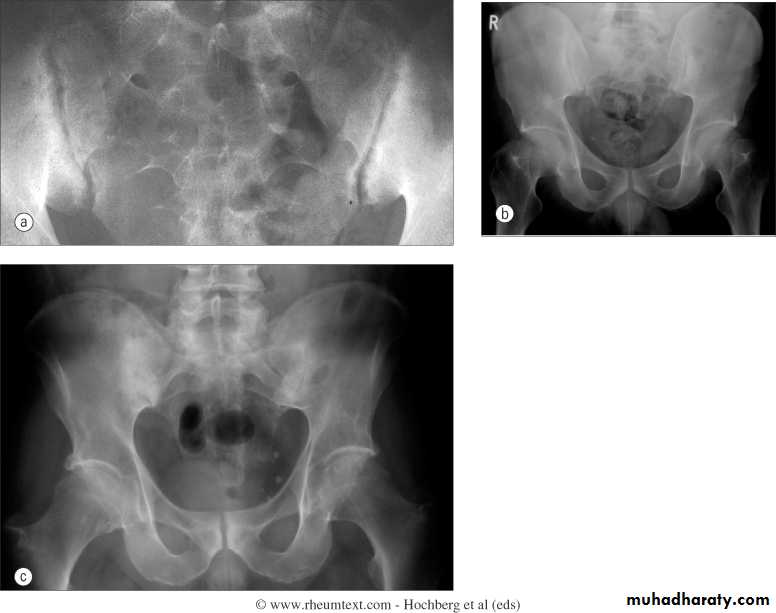

Sacriliac joints

Are the initial site of involvement(bilateral symmeterical)Erosions early

Sclerosis intermediate

Ankylosis late

Ankylosing Spondylitis

Erosions and sclerosis on iliac side